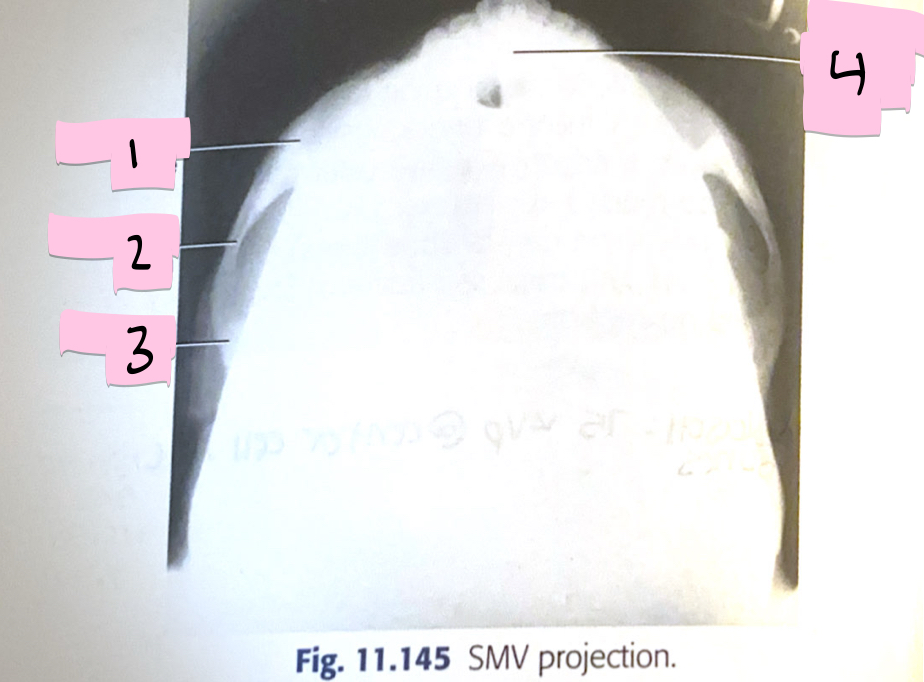

What is 1 pointing to?

Zygomatic bone

What is 2 pointing to?

Zygomatic arch

What is 3 pointing to?

Temporal bone

What is 4 pointing to?

Mandibular symphysis